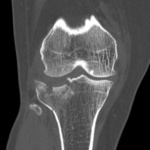

- Tibial Plateau Fractures.

if the fracture is displaced, surgery may be needed to put the bone back into the correct position and fix the bone with Plates & screws or nails for adequate healing to occur.